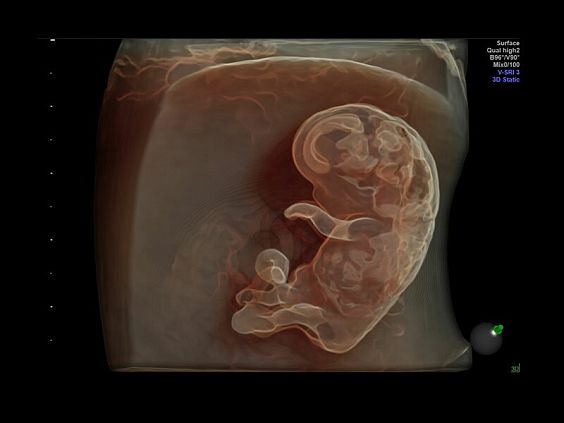

• Программа объемной визуализации плода классический HD-Live + расширенный пакет Hdlive Silhouette и Studio:

• HDlive Flow - перемещаемый источник света, совместимый с визуализацией кровотока в 3D

• HDlive Silhouette - режим "Силуэт" с подчеркиванием границ тканей и объектов, "объем в объеме"

Инновационная технология визуализации HDlive обеспечивает получение реалистических изображений за счет эффекта объемного зрения, повышая достоверность клинической оценки. Теперь режим HDlive дополняют две новые функции:

• Технология HDlive Silhouette — задает разный уровень прозрачности, помогая выявлять контуры внутренних структур и точнее оценивать состояние плода в первом триместре.